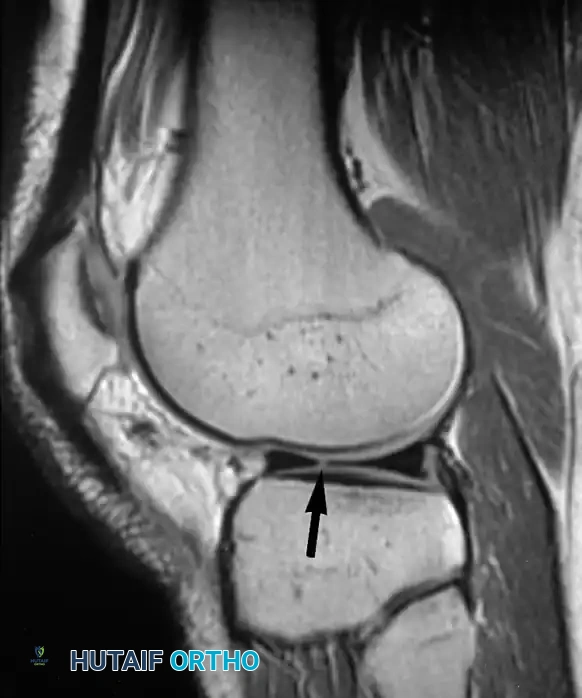

تقييم الغضاريف الهلالية

تتسبب الحالات المرضية للغضروف الهلالي في نسبة كبيرة من آلام الركبة والإعاقة الحركية. تظهر الغضاريف الهلالية الطبيعية في الرنين المغناطيسي كأشكال مثلثة داكنة اللون. عندما يحدث تغير في هذا اللون الداكن وتظهر إشارات مضيئة داخله، يصنف أطباء الأشعة هذه التغيرات إلى ثلاث درجات:

- الدرجة الأولى: مناطق دائرية من الإشارة المتزايدة داخل الغضروف.

- الدرجة الثانية: مناطق خطية من الإشارة المتزايدة لا تصل إلى السطح.

- الدرجة الثالثة: خط غير طبيعي يمتد ليصل إلى السطح المفصلي العلوي أو السفلي.

من المهم جدا للمرضى أن يعرفوا أن الدرجة الأولى والثانية لا تمثل تمزقا حقيقيا، بل هي مجرد تغيرات تنكسية طبيعية لا تحتاج لتدخل جراحي. فقط الدرجة الثالثة هي التي تعبر عن تمزق حقيقي في الغضروف.

يجب تحديد التمزق بدقة من حيث موقعه وشكله سواء كان أفقيا، عموديا، معقدا، أو شعاعيا.